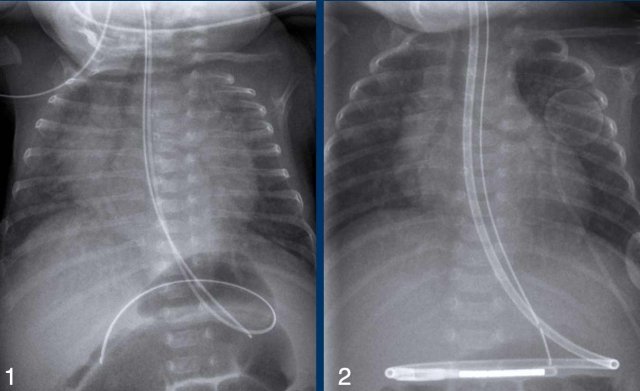

One day old boy, gestational age 25 weeks and 5 days.

• Grade 4 RDS with complete opacification of left lung and right upper lobe.

• After one bolus of surfactant the right lower lobe and the middle lobe are aerated.

• Good position of ETT and umbilical artery line.

• Malposition of the umbilical vein line in the portal vein. This should be removed.